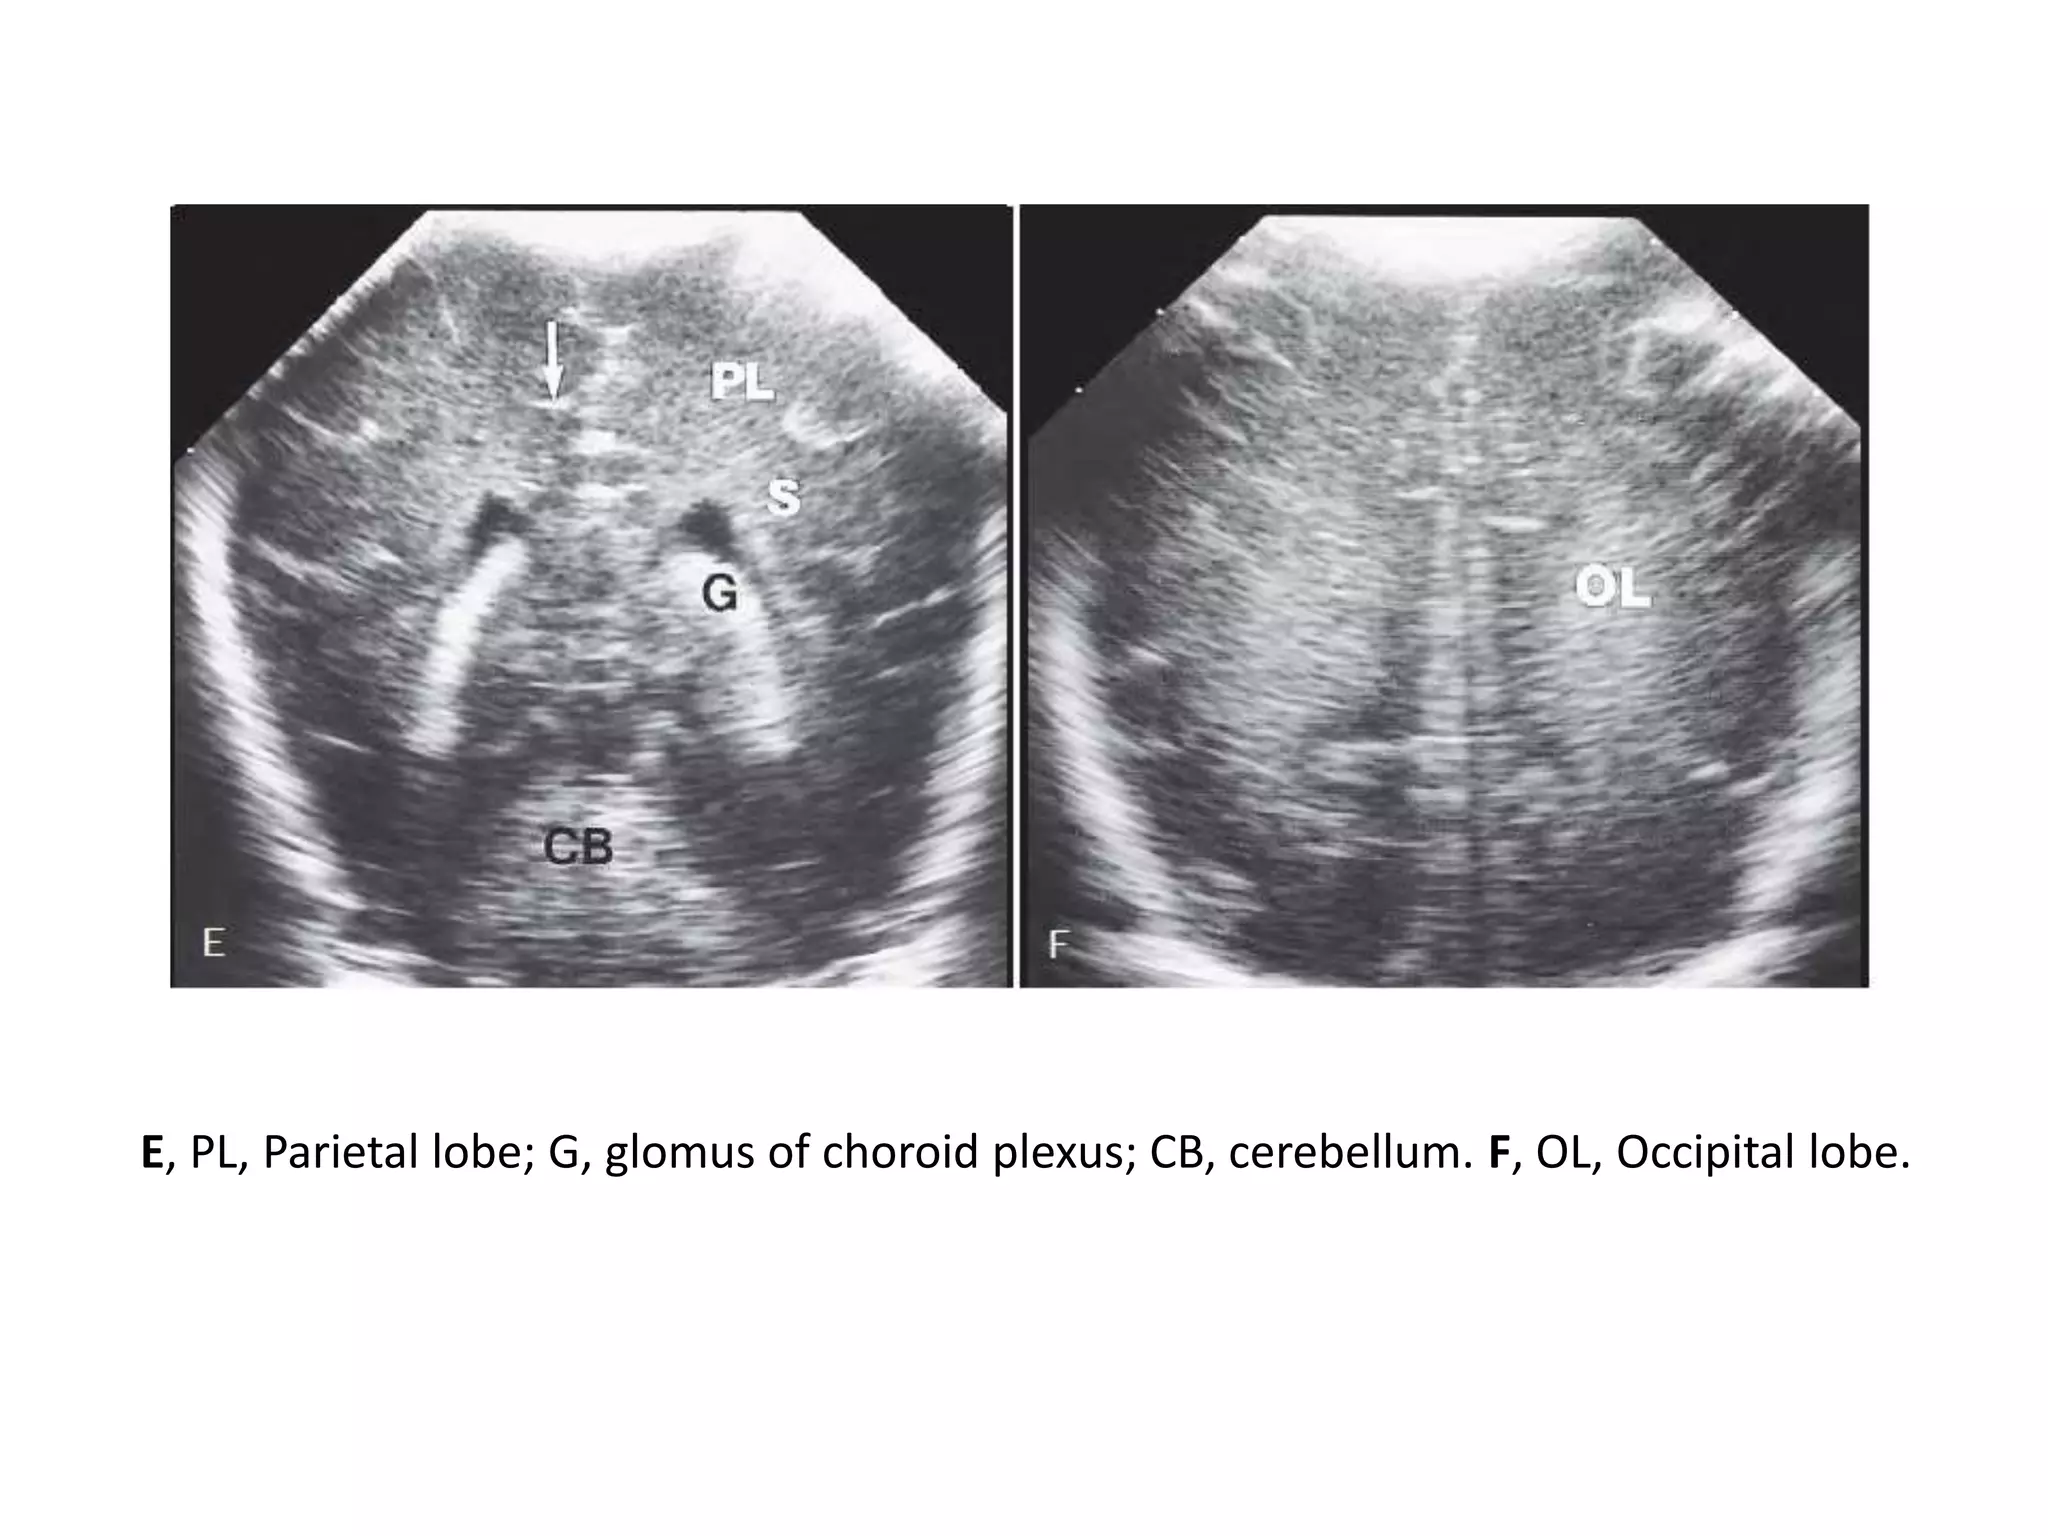

Coronal brain ultrasound images: normal full-term infant. Anterior to posterior corresponds to sections A to

F - A, FL, Frontal lobes; black arrow, interhemispheric fissure. B, P, Putamen; C, caudate nucleus; f,

frontal horns of lateral ventricles; TL, temporal lobe; arrowhead, corpus callosum; closed arrow, sylvian

fissure; open arrow, bifurcation of internal carotid artery. (On images A and B black arrow represents

interhemispheric fissure.) C, B, Brainstem; 3, location of third ventricle (third and fourth ventricles are

difficult to see in normal patients on coronal cuts). D, S, Centrum semiovale; b, body of lateral ventricle; c,

choroid plexus; T, thalamus; V, vermis of cerebellum; curved arrow, tentorium cerebelli; straight white

arrow, cingulate sulcus.

E, PL, Parietal lobe; G, glomus of choroid plexus; CB, cerebellum. F, OL, Occipital lobe.

E, PL, Parietallobe; G, glomus of choroid plexus; CB, cerebellum. F, OL, Occipital lobe.